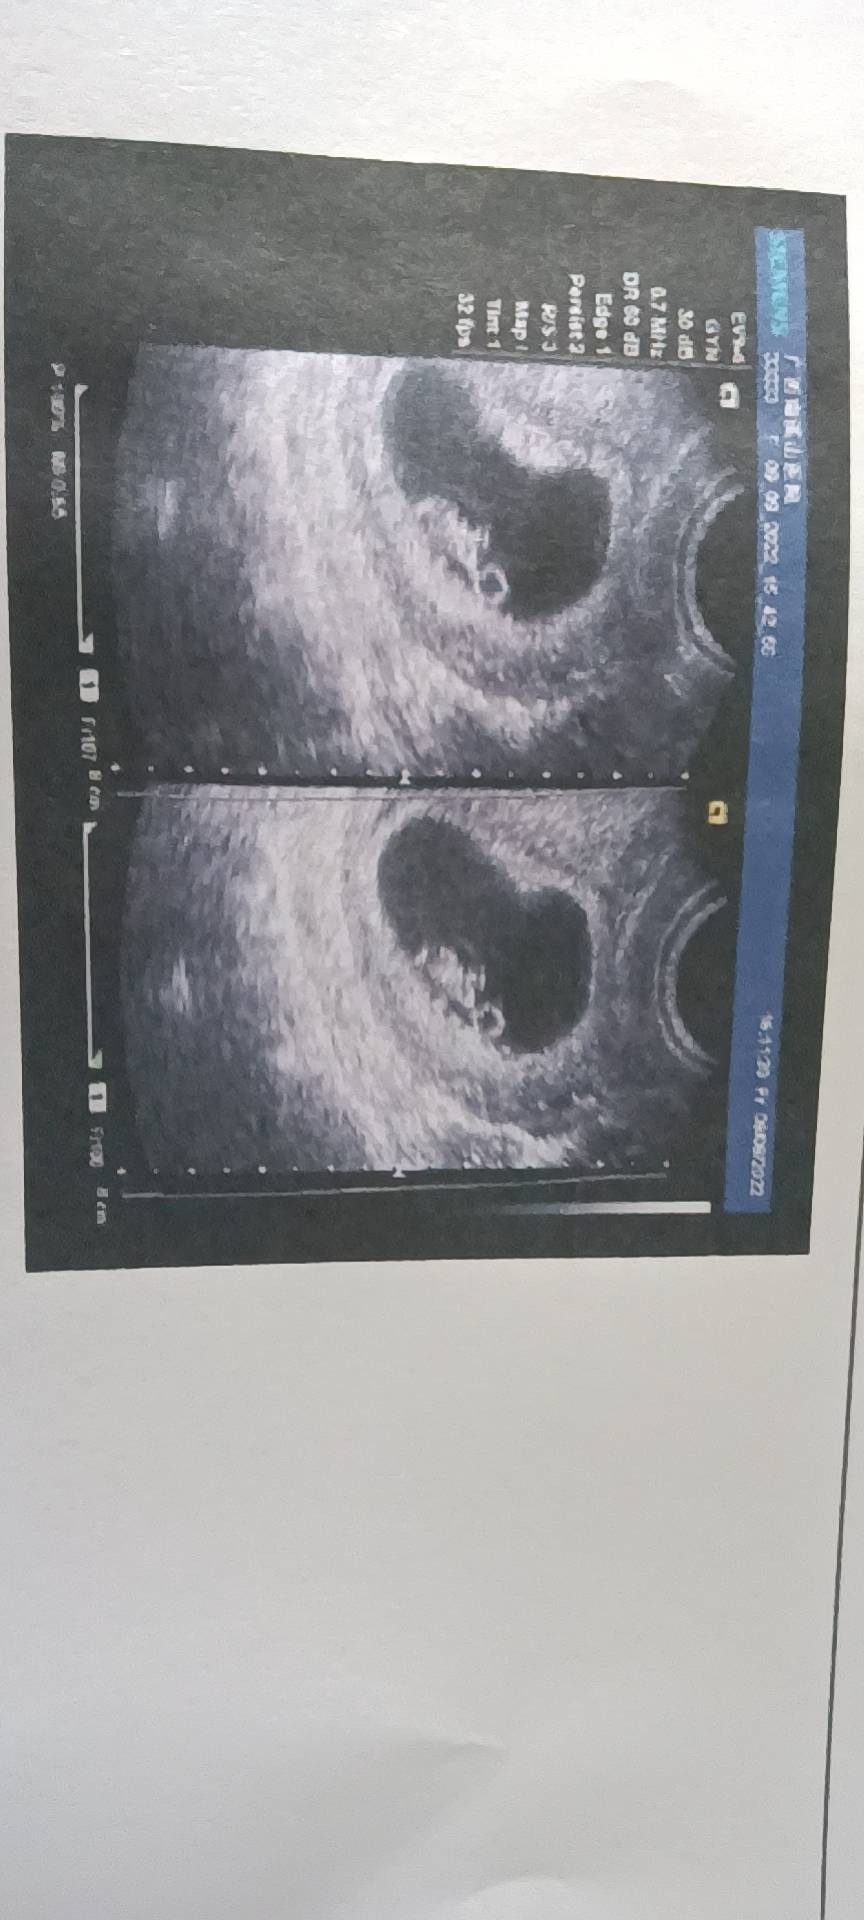

以前我咋没看到有个小人人😂这次叫小泳泳有什么故事吗?